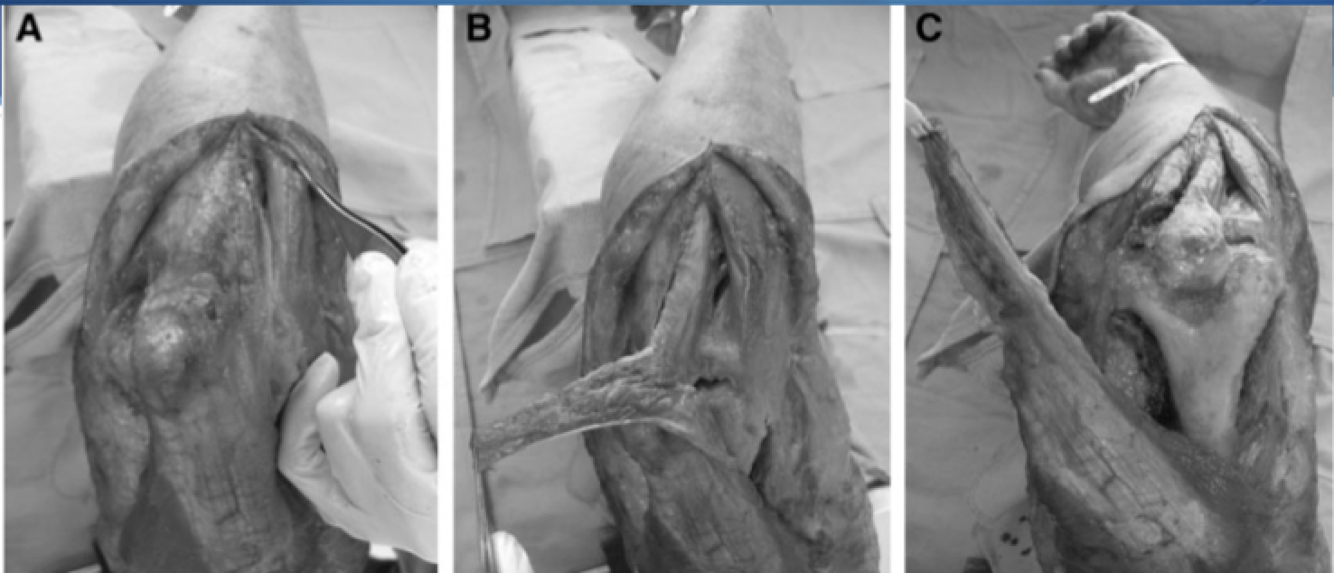

Boyd Approach

Interval: Between both anconeus (radial n.) and ECU (PIN), and subcutaneous boarder of ulna/ FCU (ulnar n.)

Approach: Develop interval between both anconeus and ECU, and lift both anteriorly. Release supinator subperiosteally.

Dangers: Increased risk of synostosis.

Kocher Approach

Interval: Anconeus (radial n.) & ECU (PIN)

Approach: Look for fat stripe between the two. Anconeus fibres will run obliquely. Will need to elevate some of supinator to reveal distal insertion of LUCL on crestor supinatore.

Dangers: PIN, LUCL

* can extend proximally by detatching anconeus from its origin on the distal humerus, and triceps from lateral intramuscular septum.